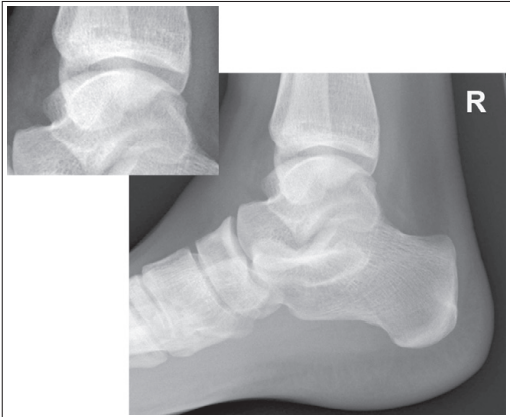

What are issues with this mortise ankle?

Insufficient obliquity/ under-rotated

the tibia superimposes more than 1/4 of the fibula, and the lateral and medial mortises are closed

What are the issues with this mortise ankle?

the tibia superimposes less than 1/4 of the fibula, and the lateral and medial mortises are closed

Excessive obliquity/ over-rotated